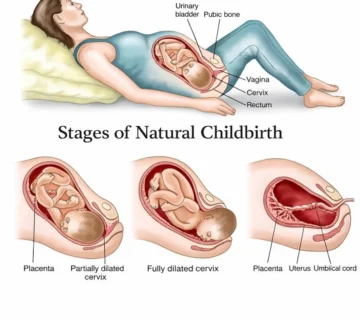

Қисми болоии ҳомилапазирӣ, ки гардани бачадон ном дорад, мушакӣ ва чандир аст ва метавонад то 100 маротиба зиёдтар аз андозаи аслиаш дароз шавад, то кӯдакро нигоҳ дорад. Ҳоло бачадон таҳти устухони камар аст, вале дар чанд ҳафтаи оянда болотар баромада, байни меъда ва рӯдаҳо ҷойгир мешавад.